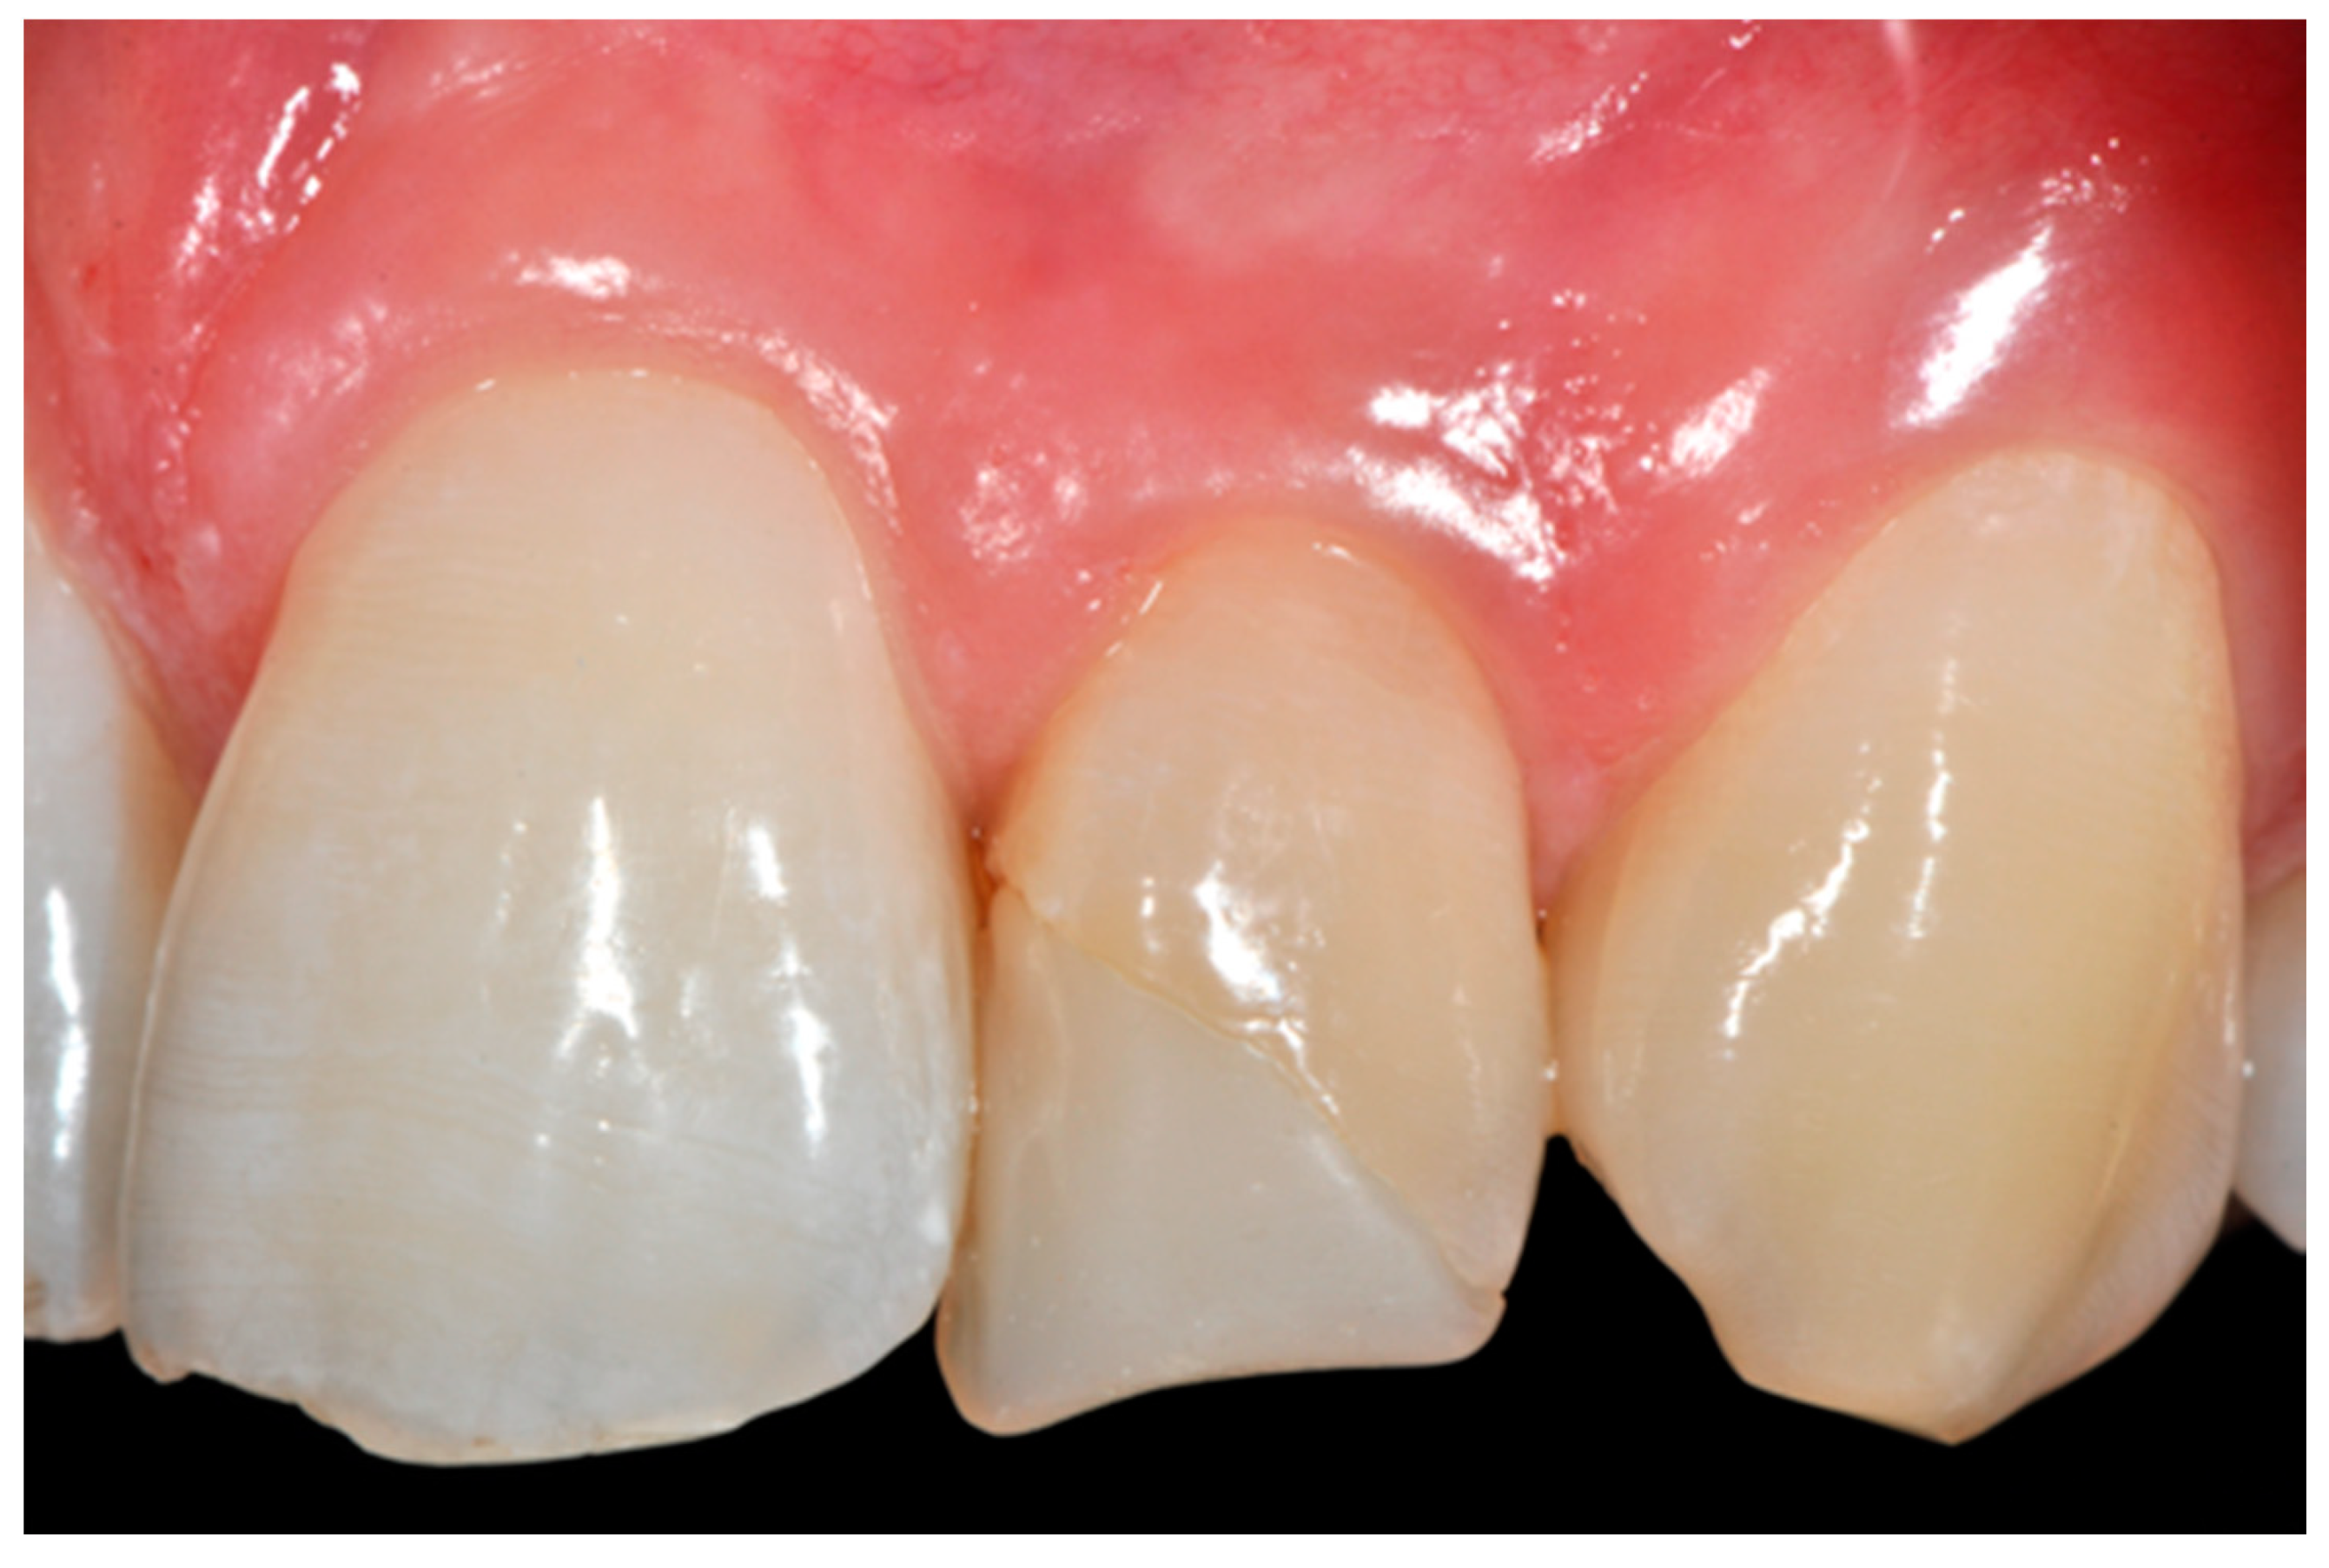

Figure 30.

Initial clinical situation. Reprinted from Restauri diretti nei settori anteriori, G. Paolone, S. Scolavino, © 2021, with permission from Quintessence Publishing Italy.